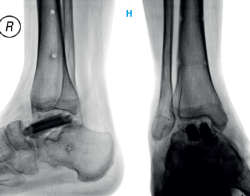

Figura 5. Escisión completa del astrágalo. Estabilización con fijador externo y colocación de espaciador de polimetilmetacrilato moldeado con forma de astrágalo.

Ante la posibilidad de encontrarnos ante una neoplasia maligna y al casi no tener opción de una nueva biopsia incisional, se decide retirar el astrágalo por un abordaje anterolateral del tobillo. El astrágalo ya se encontraba deformado, con la superficie articular con signos de degeneración, inclusive con la superficie dorsal colapsada. Posteriormente se coloca un espaciador de PMM y un fijador externo (Figura 5).

Figura 7. Retirada del espaciador de polimetilmetacrilato y colocación de injerto óseo de peroné.

Tras 8 semanas, se decide retirarlo y se coloca un aparato de yeso suropédico, además de iniciar la carga parcial progresiva. En los rayos X se evidencian signos de remodelación del injerto (Figura 8). Se mantiene la inmovilización durante 2 meses y se consigue la carga total sin dolor.